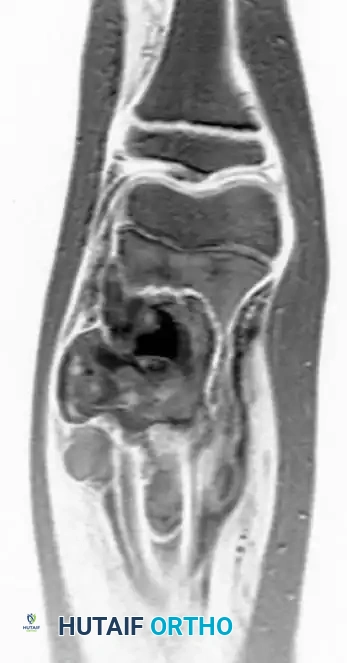

Intraoperative Imaging and Margin Assessment

Continuous intraoperative assessment using fluoroscopy and frozen section pathology is mandatory. The following images demonstrate various stages of complex upper extremity resections, allograft preparations, and prosthetic implantations across the humerus and elbow joint.

Distal Humerus and Elbow Reconstruction

When tumors involve the distal humerus, resection often requires sacrifice of the collateral ligaments and the articular surface of the elbow. Reconstruction is typically achieved using a linked, semi-constrained total elbow arthroplasty designed for oncologic defects.